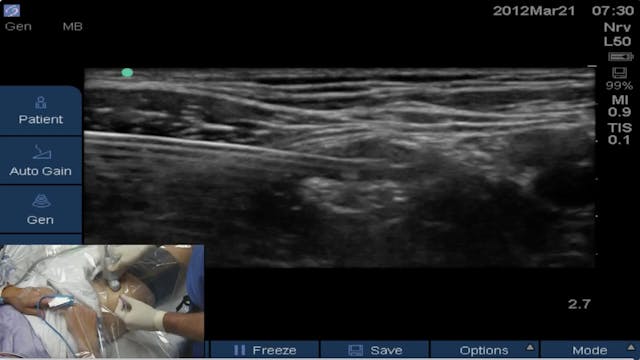

Block of the Day #9: Brandon Winchester places an US-guided femoral catheter at Andrews Institute for ACL reconstruction.